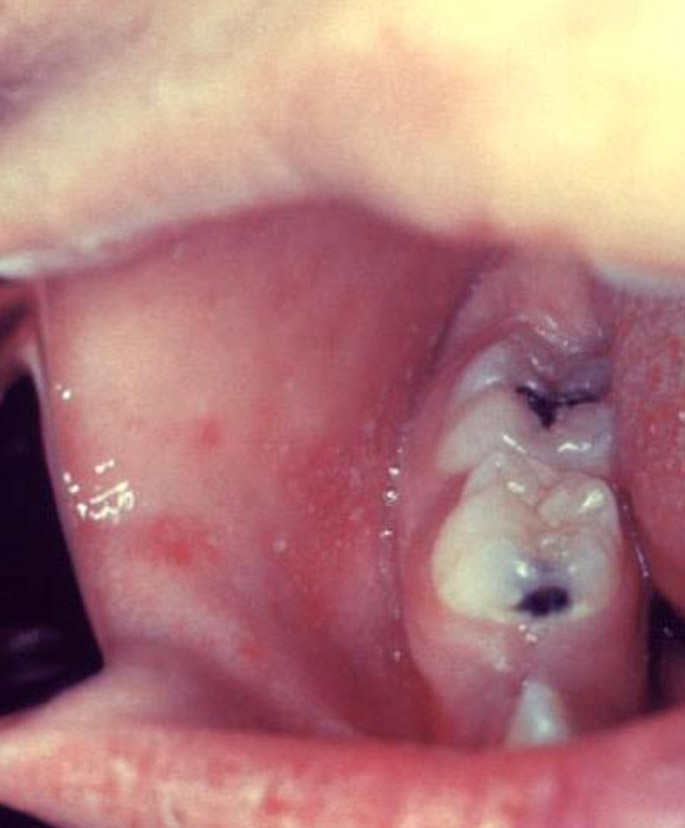

De 2 a 3 días después del comienzo de los síntomas: manchas de Koplik

Pequeñas manchas blancas (manchas de Koplik) podrían aparecer dentro de la boca dos a tres días después del comienzo de los síntomas.

En el tercer día previo a la erupción, este paciente presentó "manchas de Koplik", que son indicativas del comienzo del sarampión.